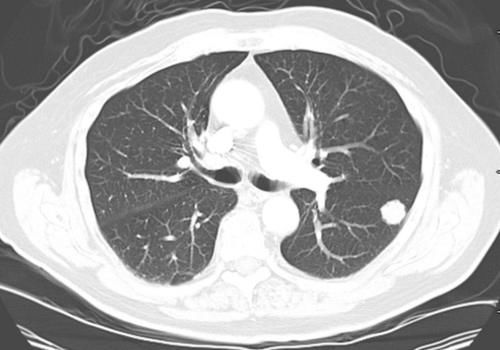

如果在肺部检查时,发现数据信号异常,应该根据结节的状况,来做出正确的判断。